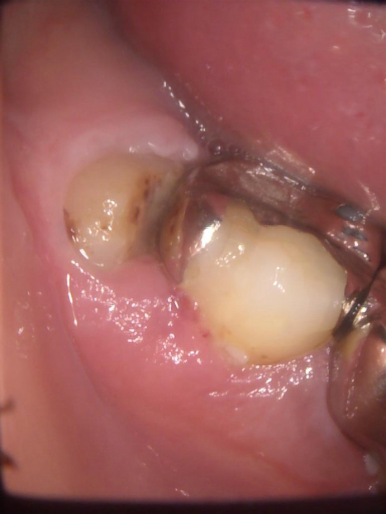

左端の歯が親知らずです。ブラッシングが難しく、沢山磨き残しがあります。手前の歯も虫歯になっています。

一番奥の歯が親知らずです。汚れがたまって腫れています。